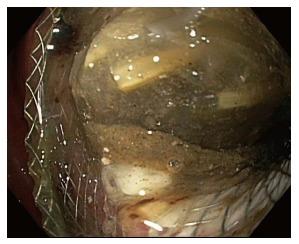

For patients recovering from acute pancreatitis, the development of a pancreatic fluid collection (PFC) predicts a more complex course of recovery, and introduces difficult management decisions with regard to when, whether, and how the collection should be drained. Most PFCs resolve spontaneously and drainage is indicated only in pseudocysts and walled-off pancreatic necrosis when the collections are causing symptoms and/or local complications such as biliary obstruction. Historical approaches to PFC drainage have included surgical (open or laparoscopic cystgastrostomy or pancreatic debridement), and the placement of percutaneous drains. Endoscopic drainage techniques have emerged in the last several years as the preferred approach for most patients, when local expertise is available. Lumen-apposing metal stents (LAMS) have recently been developed as a tool to facilitate potentially safer and easier endoscopic drainage of pancreatic fluid collections, and less commonly, for other indications, such as gallbladder drainage. Physicians considering LAMS placement must be aware of the complications most commonly associated with LAMS including bleeding, migration, buried stent, stent occlusion, and perforation. Because of the patient complexity associated with severe pancreatitis, management of pancreatic fluid collections can be a complex and multidisciplinary endeavor. Successful and safe use of LAMS for patients with pancreatic fluid collections requires that the endoscopist have a full understanding of the potential complications of LAMS techniques, including how to recognize and manage expected complications.

对于急性胰腺炎康复期的患者,胰液积聚(PFC)的出现预示着康复过程会更加复杂,并且在何时、是否以及如何引流积聚物方面带来了艰难的管理决策。大多数PFC会自行消退,仅在假性囊肿和包裹性胰腺坏死且积聚物引起症状和/或局部并发症(如胆道梗阻)时才需要引流。PFC引流的传统方法包括手术(开放或腹腔镜囊肿胃造口术或胰腺清创术)以及放置经皮引流管。在过去几年中,当有当地专业技术支持时,内镜引流技术已成为大多数患者的首选方法。管腔对合金属支架(LAMS)最近已被开发出来,作为一种有助于更安全、更容易地进行胰液积聚内镜引流的工具,较少用于其他适应症,如胆囊引流。考虑放置LAMS的医生必须了解与LAMS最常见相关的并发症,包括出血、移位、支架埋入、支架阻塞和穿孔。由于与重症胰腺炎相关的患者情况复杂,胰液积聚的管理可能是一项复杂的多学科工作。成功且安全地将LAMS用于胰液积聚患者要求内镜医师充分了解LAMS技术的潜在并发症,包括如何识别和处理预期并发症。